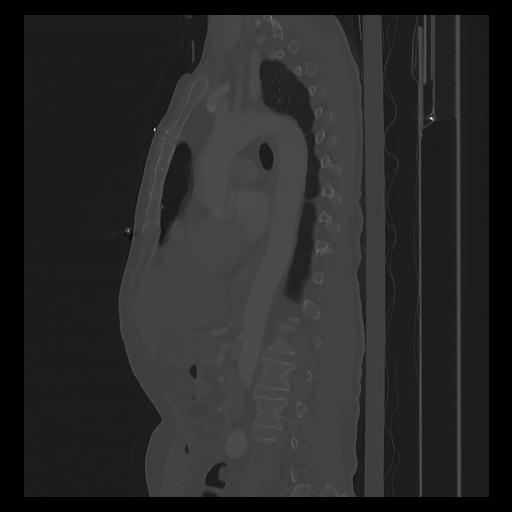

33 PULMON,CE,Sagittal,3.000,PULMON,Sagittal,